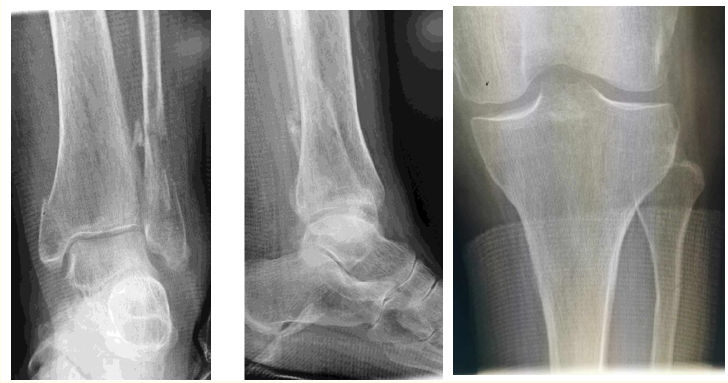

A Maisonneuve Like Bimalleolar Fracture: A Case Report

Ekkehard Pietsch. 14(4): 32-36.